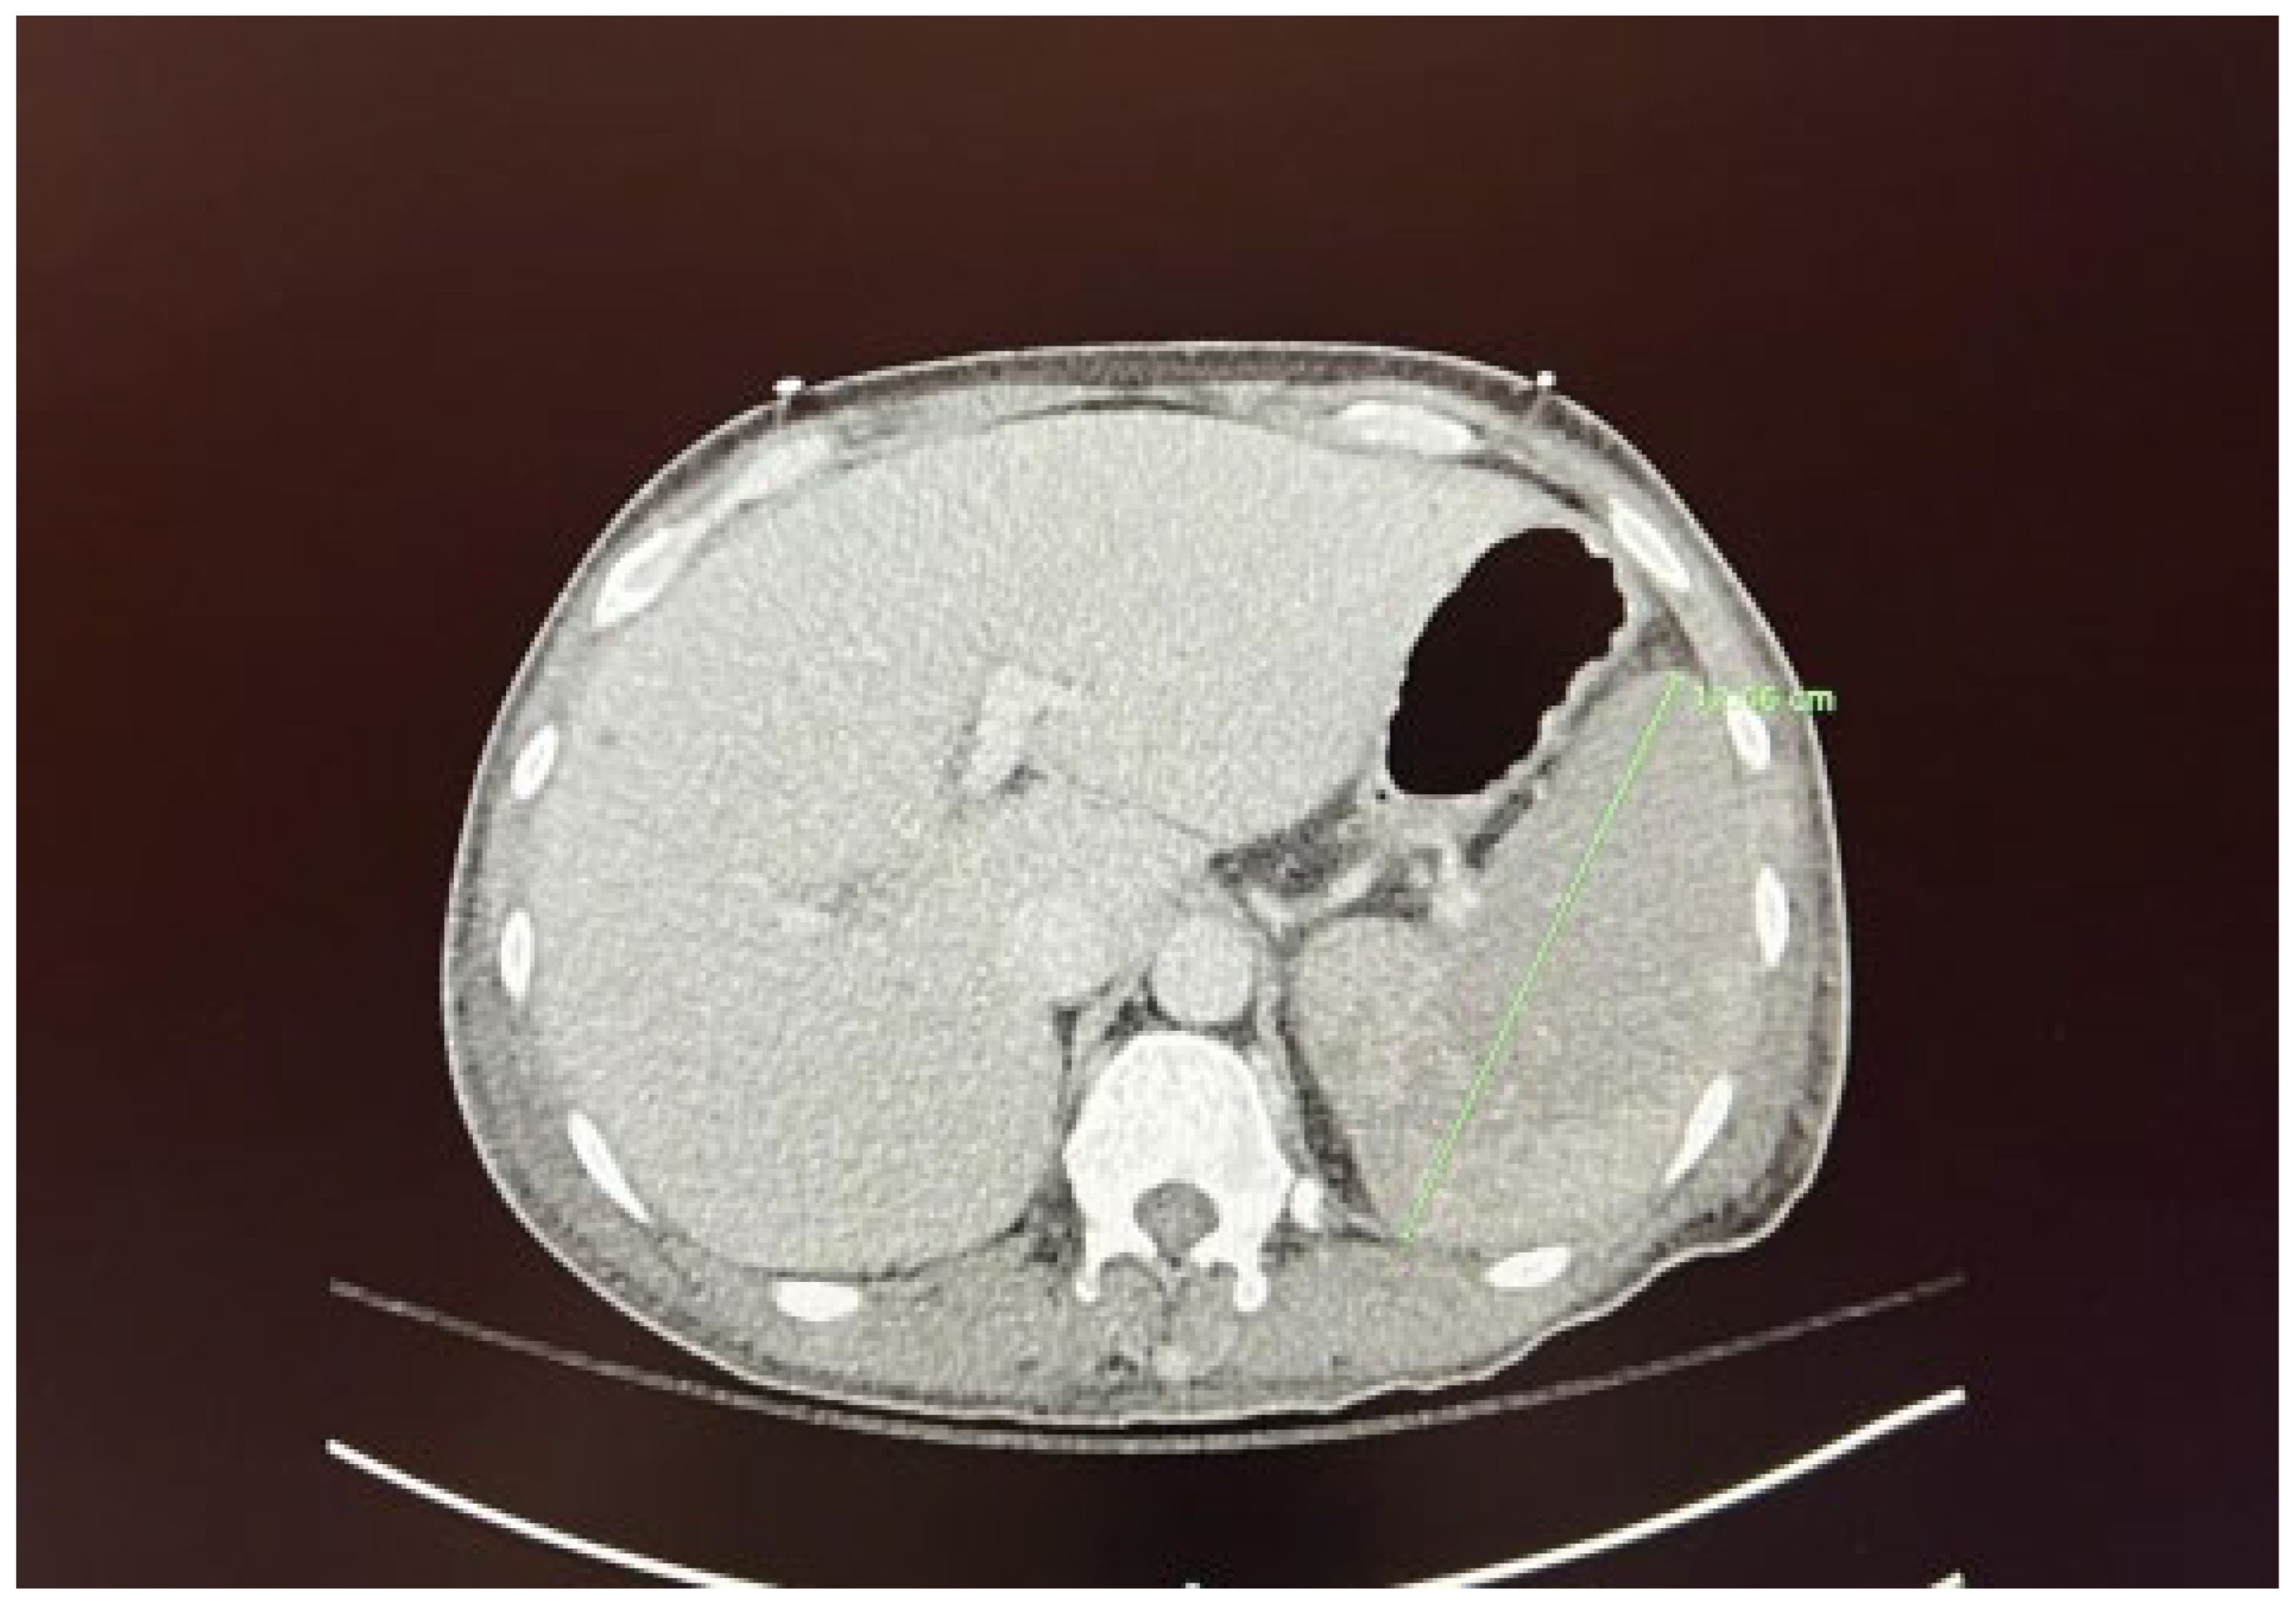

We present the case of a 67-year-old male diagnosed with high-risk chronic myelomonocytic leukemia (CMML) in October 2023. The patient presented to the hematology/oncology clinic exhibiting symptoms of malaise, dizziness, chills, tachycardia, and hypotension, which raised concerns about sepsis. Following the administration of 1 liter of intravenous fluids and cefepime, he was subsequently referred to the emergency department. Upon admission to the medicine floor, he underwent evaluation and management for sepsis and lactic acidosis. However, due to persistent hypotension necessitating vasopressor support and elevated lactic acid levels greater than 5 mmol/L, he was transferred to the medical intensive care unit. This admission marked the patient’s fourth instance of neutropenic fever since the initial diagnosis of CMML. His condition was further complicated by a peripheral blast crisis, prompting treatment with azacitidine and venetoclax, as well as the presence of pancytopenia accompanied by leukocytosis (now showing a downtrend) and severe thrombocytopenia, placing him at risk for tumor lysis syndrome. The patient had recently received chemotherapy on April 5, 2024, as well as Neulasta on April 8, 2024, for neutropenic support. He reported experiencing severe abdominal pain, rated at 8 out of 10. A computed tomography (CT) scan conducted on April 10, 2024, discounted the existence of an infectious focus and indicated hepatosplenomegaly, alongside diffuse low-density lesions in the spleen suggestive of a developing splenic infarct and minimal peri-splenic fluid accumulation; however, no active bleeding was detected (see Figure 1 and Figure 2). The critical illness of the patient appeared to be associated with the underlying CMML, recent chemotherapy, and complications from treatment, including splenic infarction, potentially attributable to the use of filgrastim.

Figure 1. - Hepatosplenomegaly with multiple splenic hypodensities consistent with splenic infarction (green arrow) after using G-CSF.